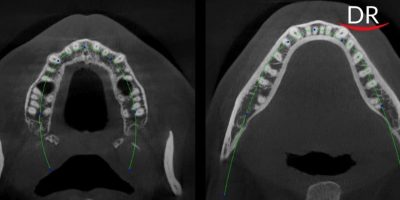

How AI ‘assist’ dentists to save tooth?

Here are some ways in which AI can potentially aid dentists and transform ... A dental practice ...